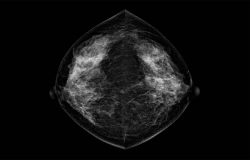

Mejorando la Experiencia de Imágenes Mamarias con un Rendimiento Premium, Potente y Continuo en Imágenes Diagnósticas.

- Sistema de mamografía digital de alto rendimiento.

- El tamaño de píxel más pequeño: 65um.

- Tecnología de alta definición.

- Visualización nítida de microcalcificaciones en imágenes mamarias.